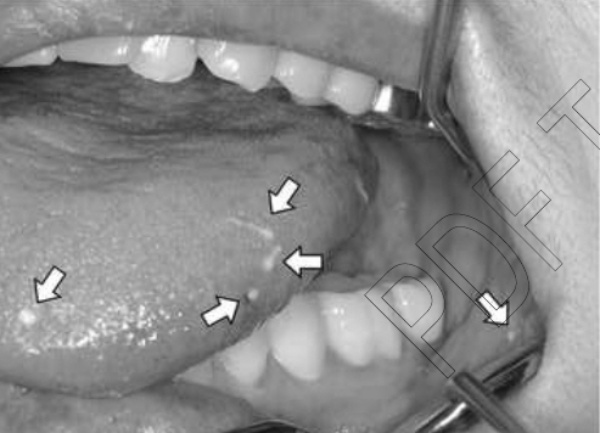

イカの赤ちゃんは口の上の部分、口の中の粘膜、頬、歯の間などで複数発見されたそうで、病院側はすぐに手術をして、発見されたイカを除去したといいます。

医師の診察を受けると、彼女の舌や歯肉に白い針のような異物が12本も突き刺さっていたというので、とんでもない事実ですね。

そのうちの一つ、「日本口腔外科学会雑誌」に掲載された論文「生イカの精莢による口腔粘膜刺創の1例」を見てみると、白い精莢が舌や頬の肉に刺さった痛々しい写真や摘出された精莢の写真が掲載されています。

精莢は5~20mmほどの長さで、先端は矢じりのようになっていて簡単には抜けない構造になっているのですが、医師による治療でも、場合によっては周囲の組織ごと除去するようです。